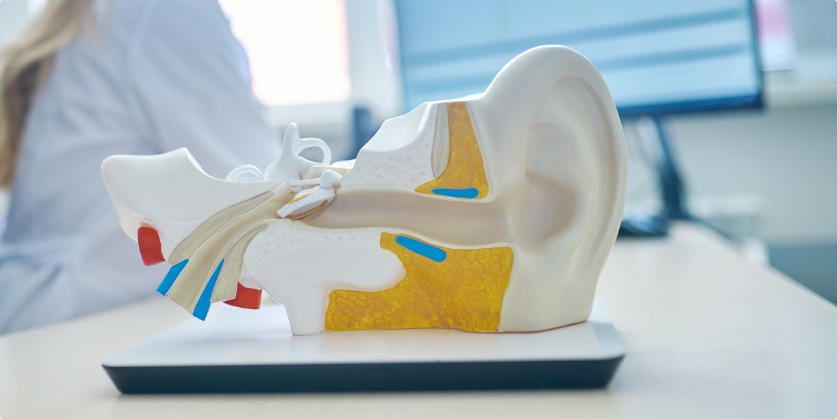

FOR IMMEDIATE RELEASE Three Physicians at Grand Rapids Ear Nose &